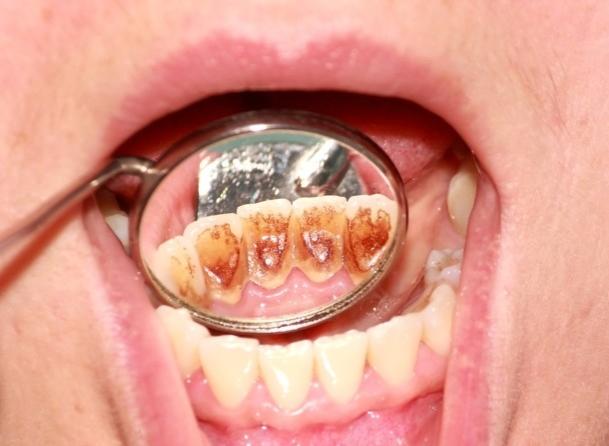

Zahnstein, der in der Regel auf der Oberfläche der weniger beanspruchten Zähne auftritt, ist bei Patienten, die auf der vorbelasteten Seite der Abfallseite kauen, sehr dick mit Zahnstein bedeckt. Darüber hinaus.Unterkiefer-Frontzähne, denn es ist die Öffnung der Speichelkanäle, reich an Mineralien, leicht zu hinterlegen und bilden Zahnstein, kann man die unteren Schneidezähne linguale Seite der gelblichen Fremdkörper zu sehen, wenn Sie Ihren Mund weit öffnen.

Achten Sie auf Ihre Mundhygiene und lassen Sie Ihre Zähne ein- bis zweimal im Jahr reinigen, sonst bilden sich große Zahnsteinbrocken, die zum Himmel stinken.